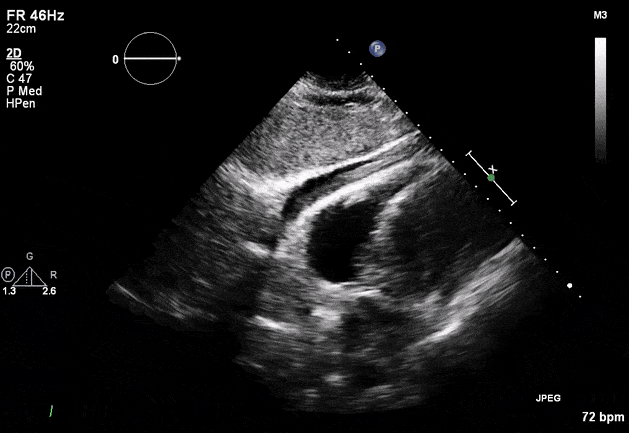

Echocardiogram

- Can be useful in assessing the severity of an RV infarct

- Visual qualitative assessment

- TAPSE (Tricuspid Annular Plane Systolic Excursion) is a validated tool to assess RV function

- Involves am M-mode at the base of the RV to assess tricuspid annular motion

- Normal ≥ 1.7 cm

- TAPSE has been validated as a predictor of heart failure and survival

- Tissue Doppler

- Systolic excursion (S’) of < 9.5 cm/sec is suggestive of RV dysfunction

RV Infarct on ECHO